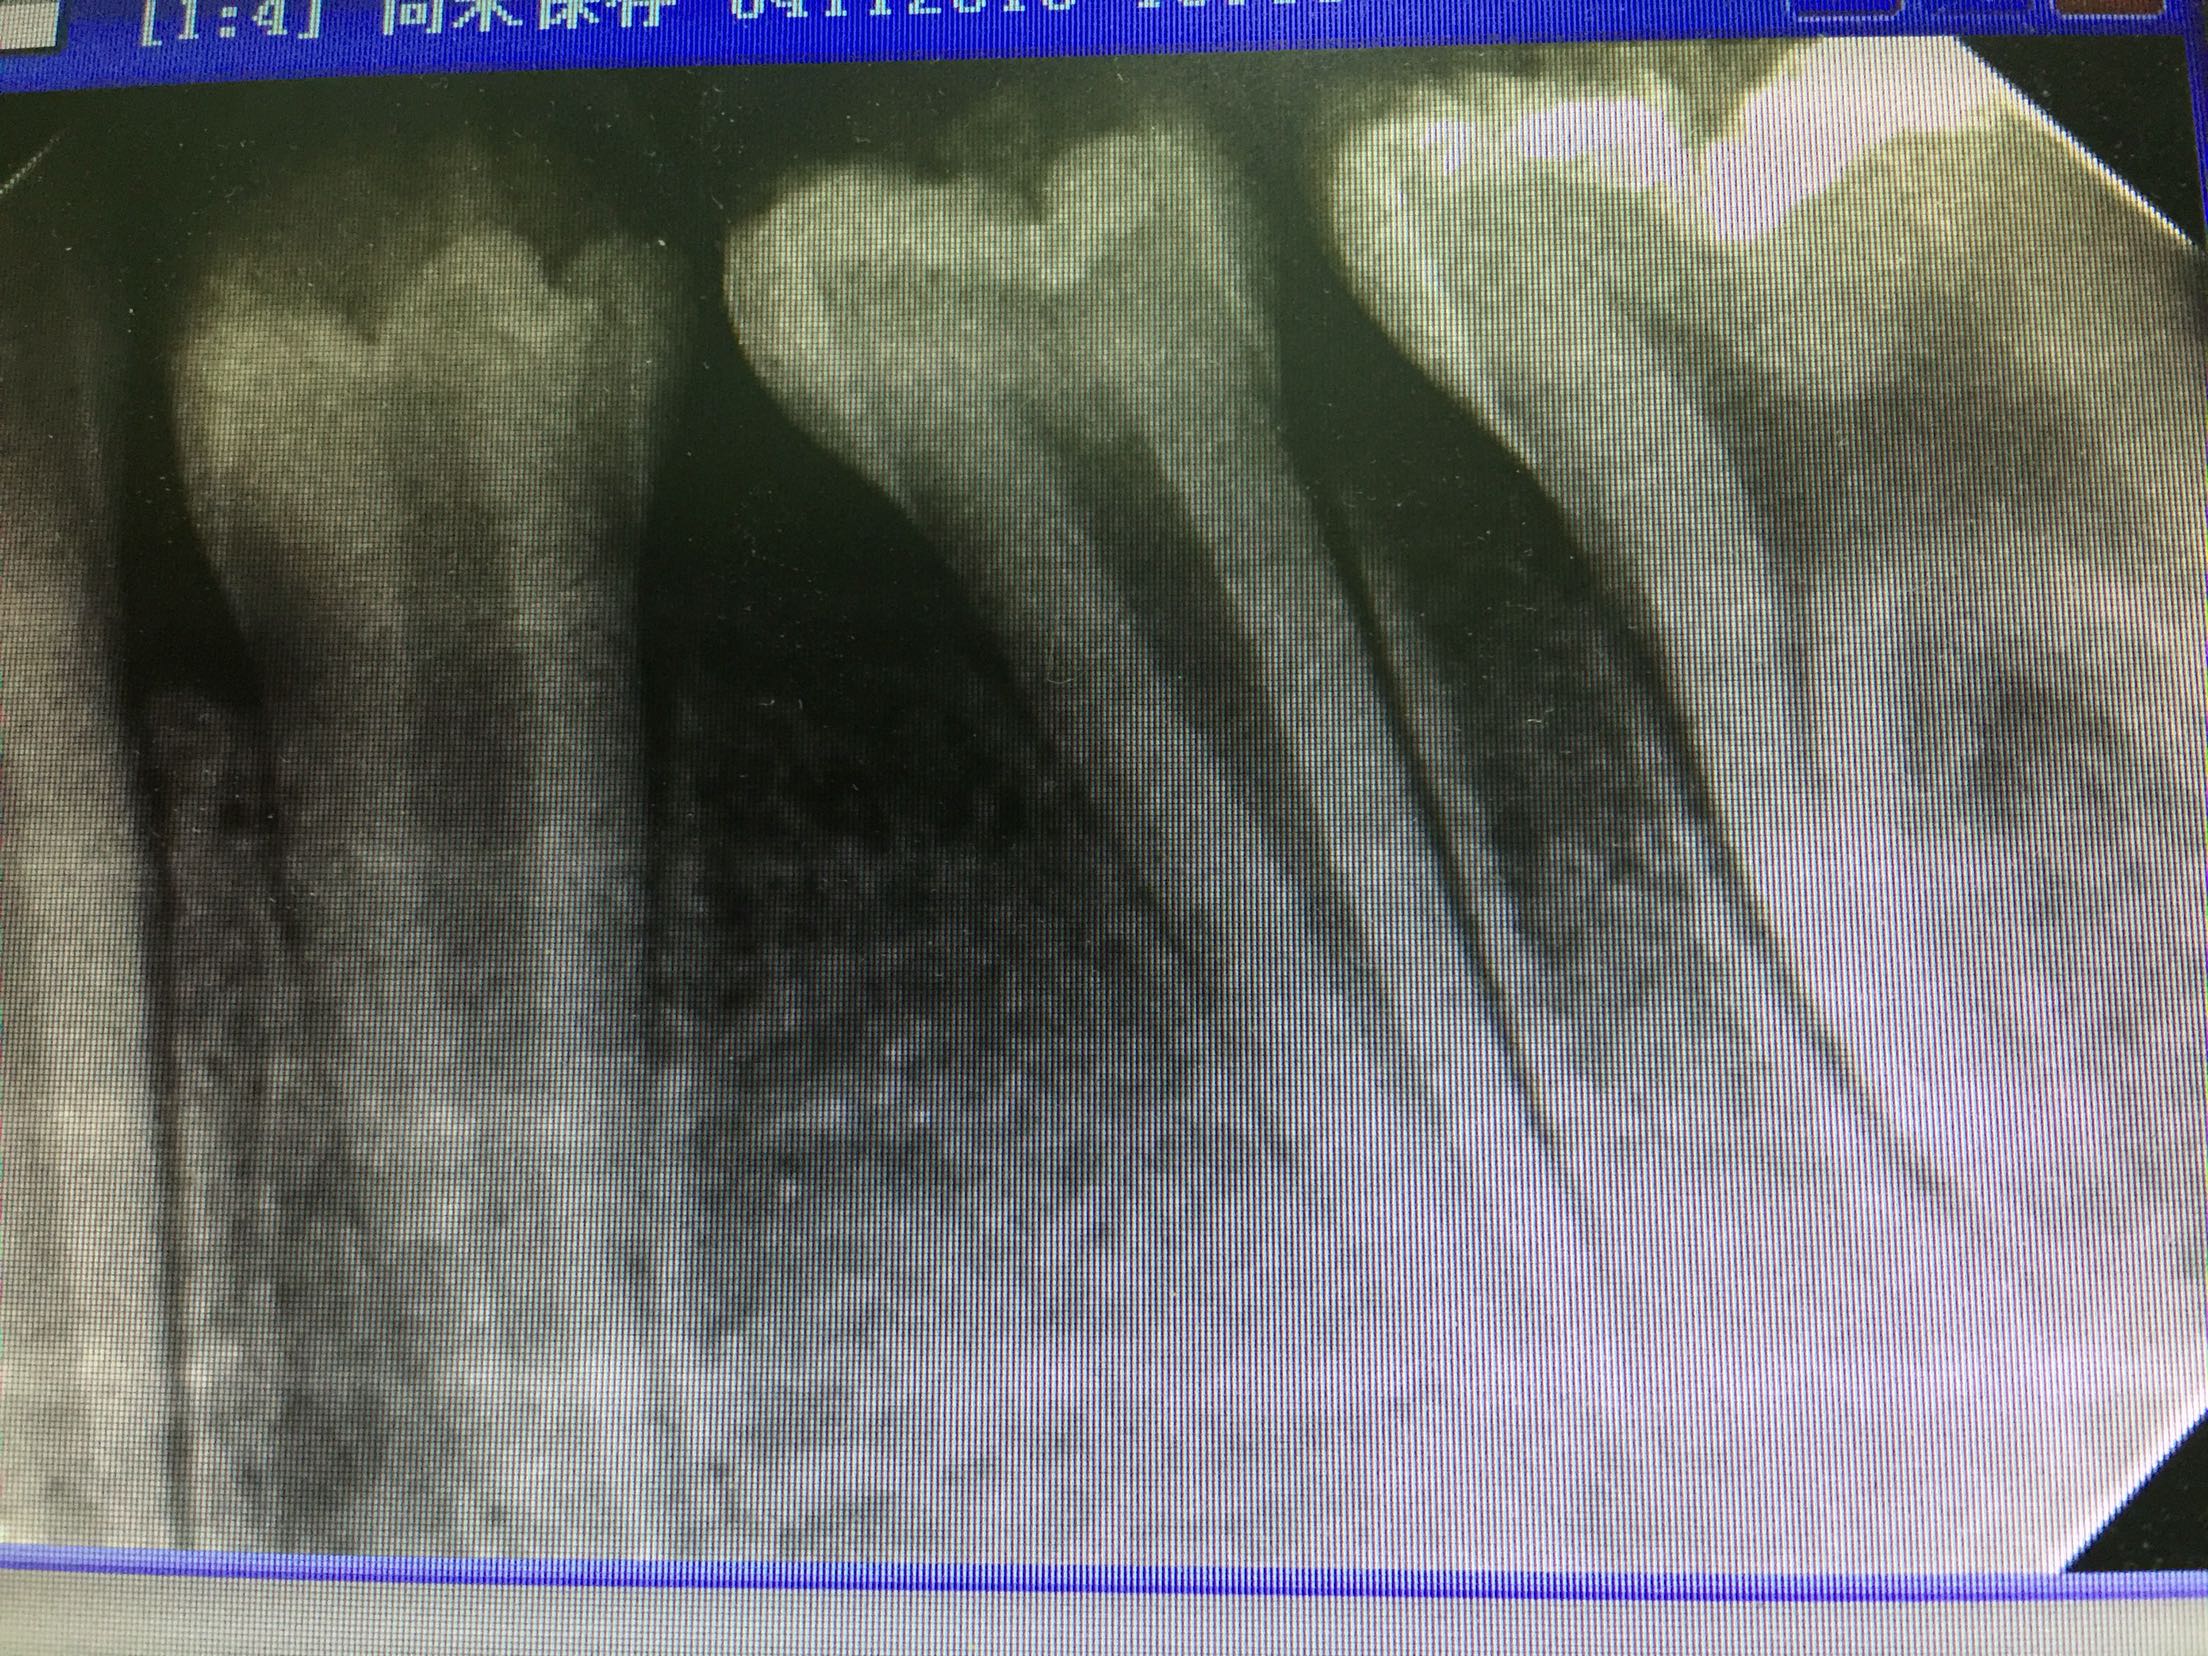

检查:35未见明显龋坏,合面可见畸形中央尖磨损,叩诊(++),松动度l度,牙龈未见明显红肿,冷诊(-)。 辅查:X线片示:35根尖基本发育完成,根尖区低密度影像。

诊断:35畸形中央尖-根尖周炎 治疗:建议35完善根管治疗,观察随诊。